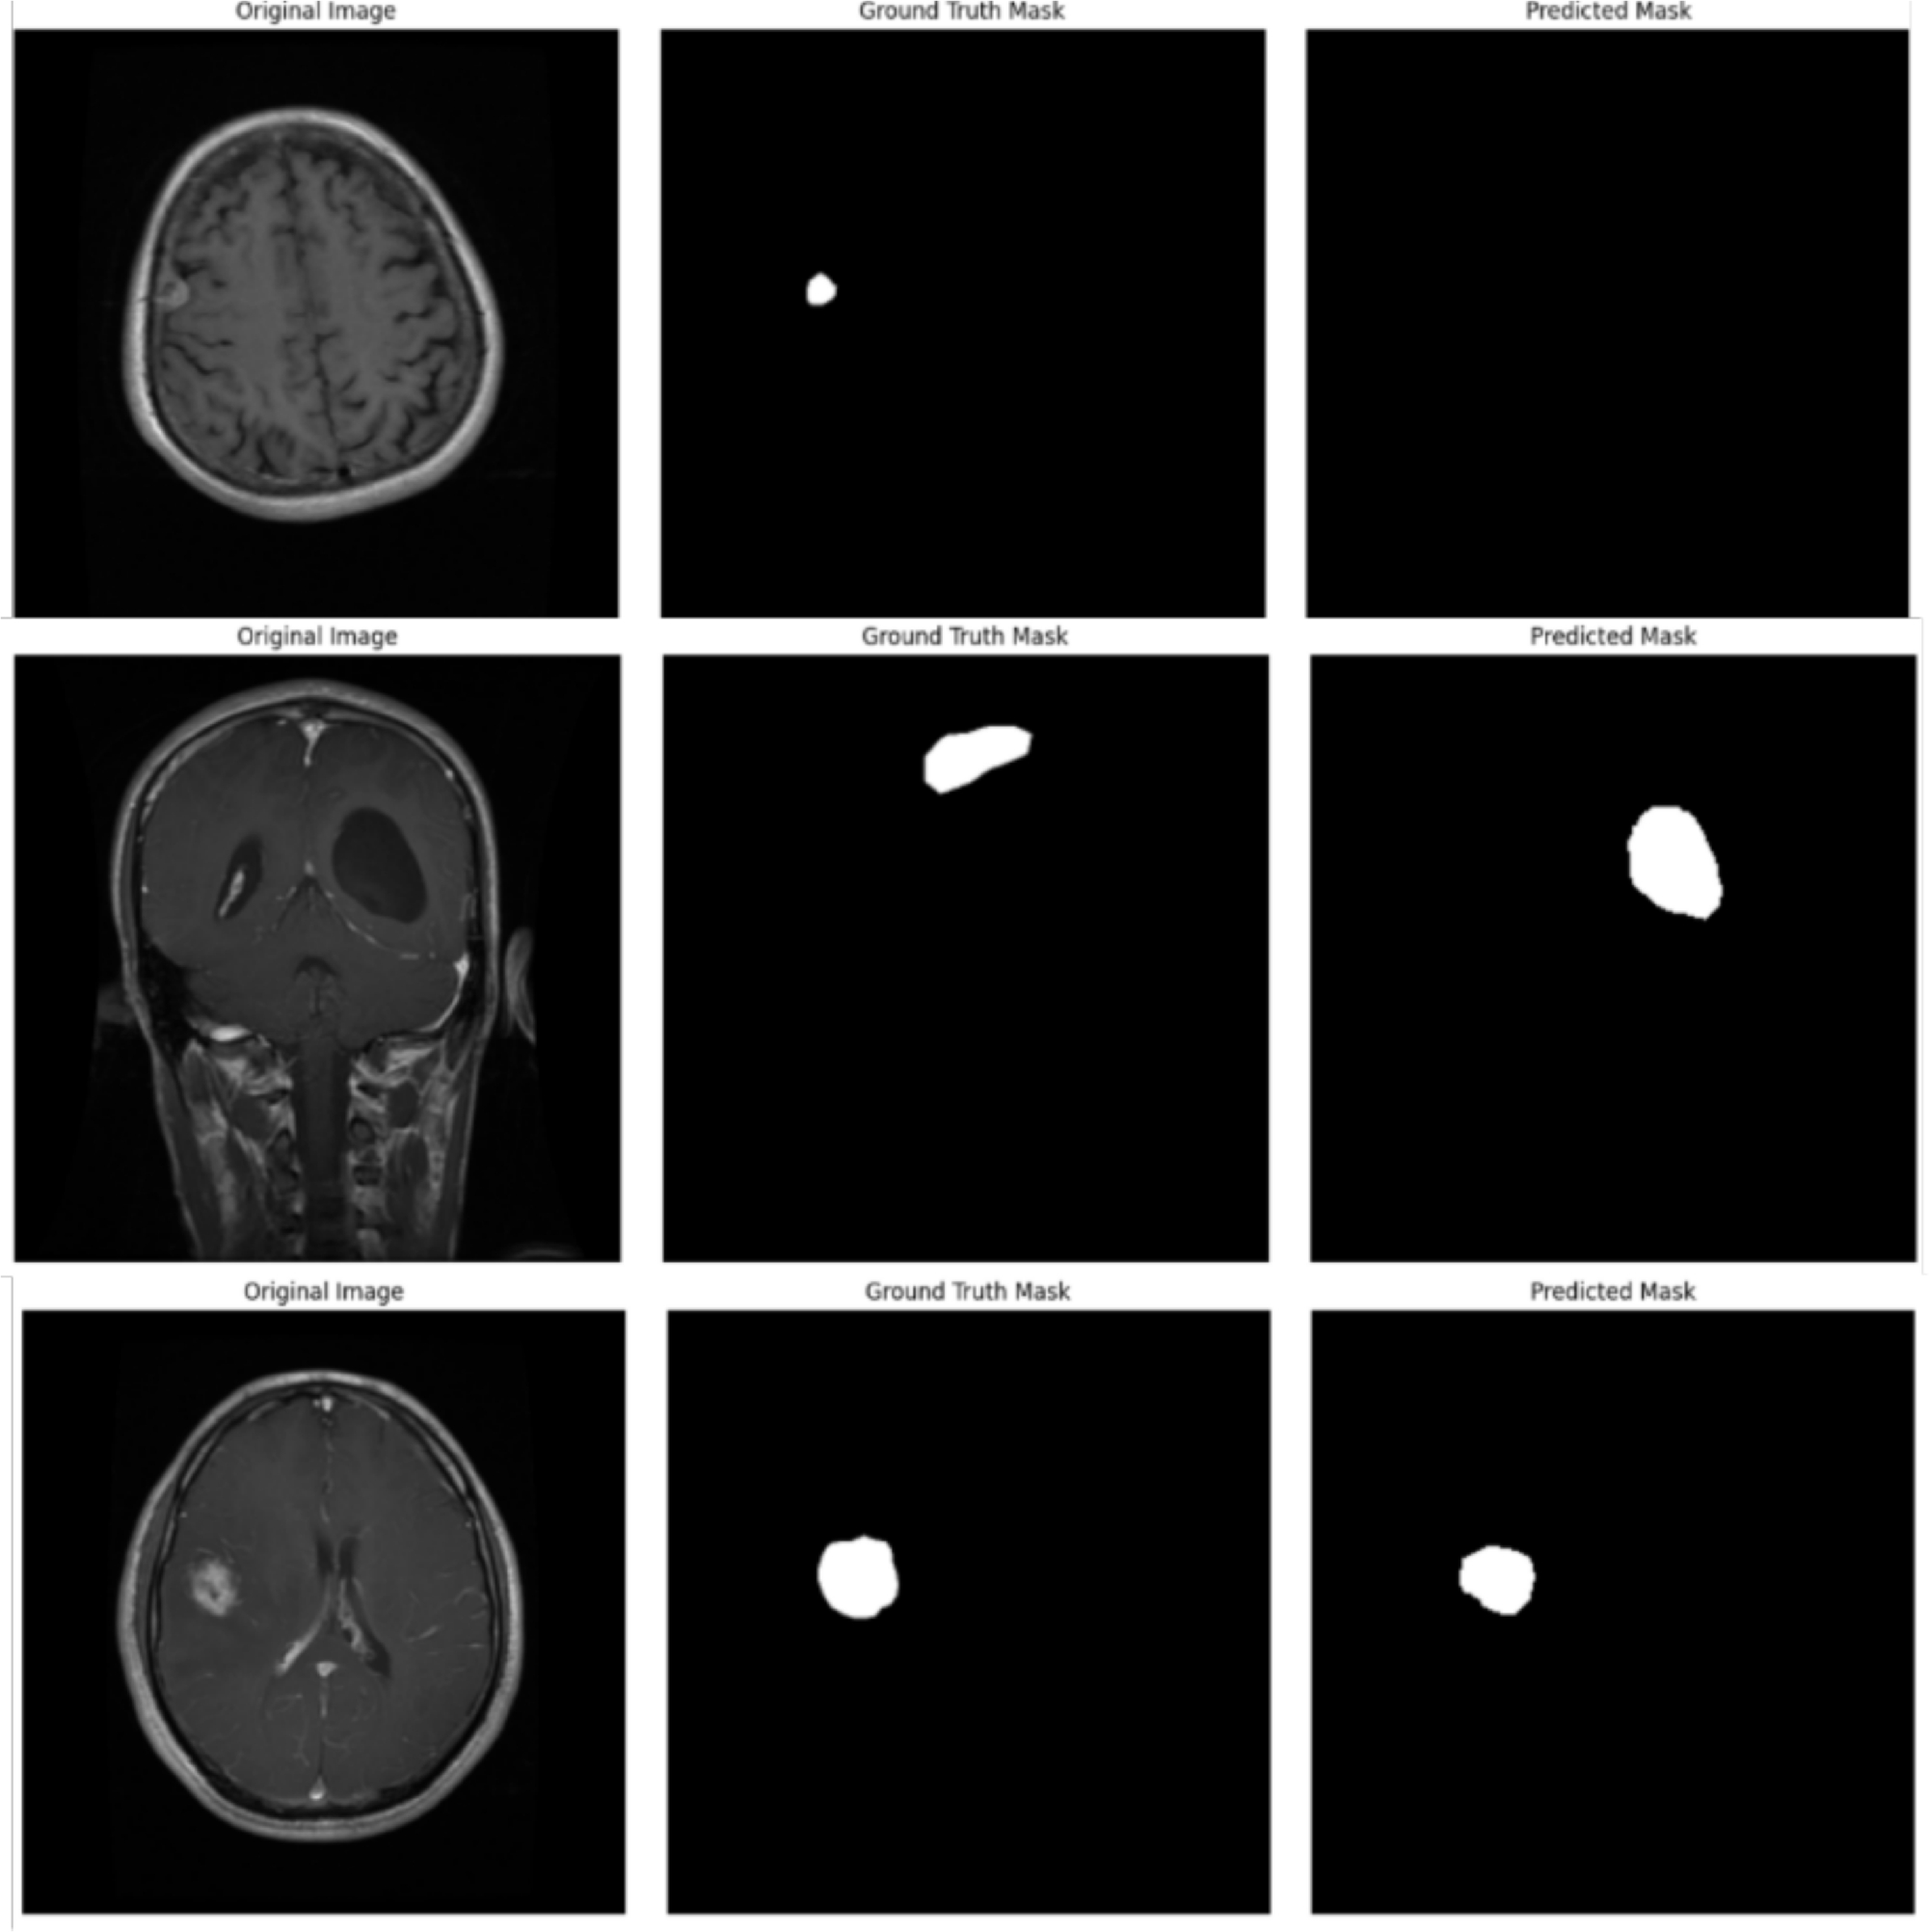

From: Brain tumor segmentation using multi-scale attention U-Net with EfficientNetB4 encoder for enhanced MRI analysis

Examples of misclassified cases.